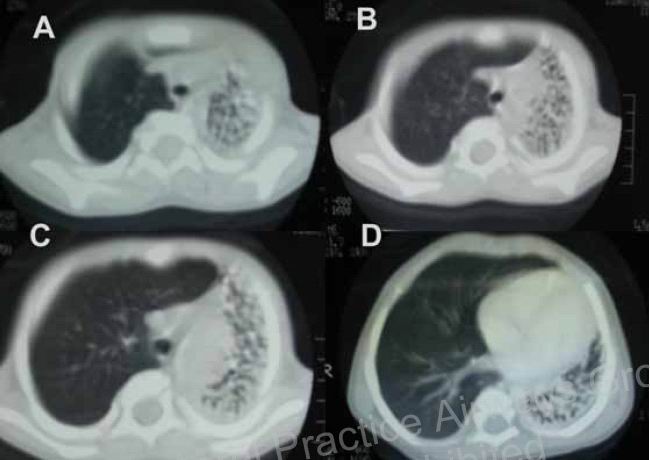

不能诊断和固定的支气管异物可能会导致严重的并发症,如肺炎、肺膨胀不全、支气管扩张等,在这例报告中,笔者发现一例较为罕见的由长期残留的支气管异物(南瓜子)导致的支气管扩张,有趣的是,由单向活瓣阻塞主支气管导致一侧全肺的支气管扩张,x线及ct要能想到,任何诊断的耽搁严重的并发症。

图:左肺多发小囊状支气管扩张。

左肺多发小囊状支气管扩张